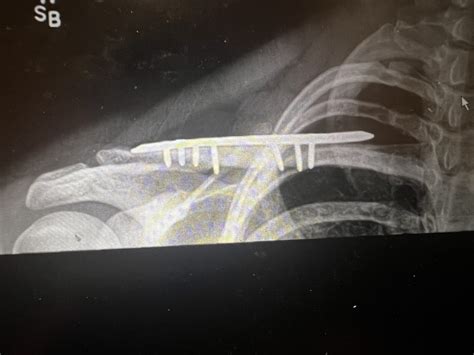

In some cases, surgery may be necessary to repair a severe collarbone fracture. Surgical options include:

• Open Reduction and Internal Fixation (ORIF): A procedure where the bone fragments are realigned and held in place with plates, screws, or pins.

• Intramedullary Fixation: A procedure where a rod is inserted into the bone to stabilize the fracture.

Surgery is typically recommended for:

• Fractures that are significantly displaced or angulated.

• Fractures that involve multiple bone fragments.

• Fractures that do not heal properly with non-surgical treatment.

📝 Note: Surgery carries risks, including infection, nerve damage, and the need for additional procedures. It is important to discuss the benefits and risks with a healthcare provider.